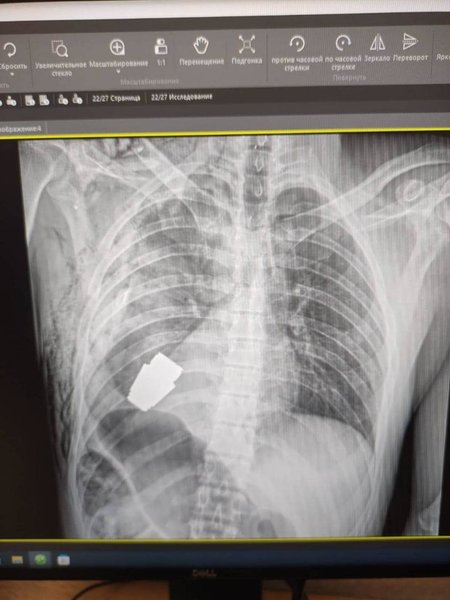

Детонирующая часть гранаты находилась чуть ниже сердца

Медики извлекли детонирующую часть гранаты, которая находилась чуть ниже сердца и оставалась взрывоопасной. Подобных операций в практике украинских врачей еще не было, подчеркнула она.

Часть гранаты застряла рядом с сердцем военного. За ходом операции наблюдали саперы, готовые вмешаться при необходимости, отметила Сливко.